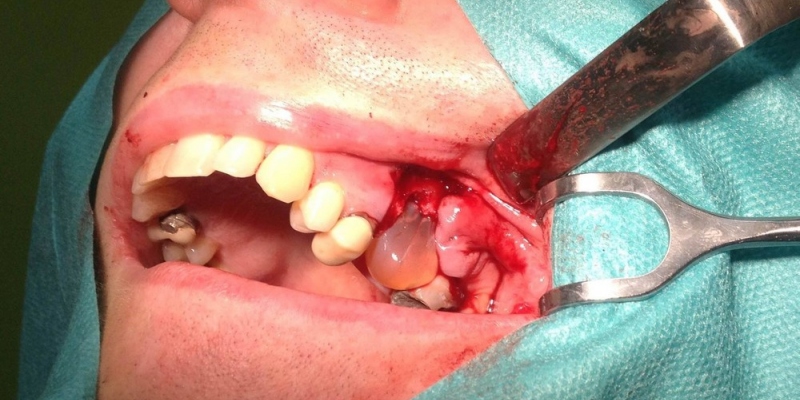

- Chirurgické extrakcie

- Cystectomia